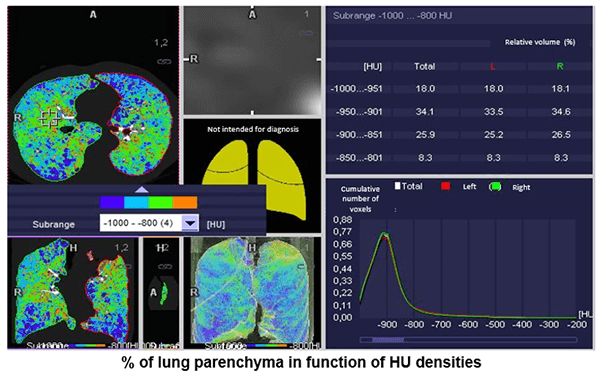

Percentage of Lung Parenchyma

Here, we can see the percentage of lung parenchyma in function of Hounsfield densities.

HU Measurements

This image shows the average density measurements in Hounsfield Units of 25%, 50 %, 75%, and 100%.